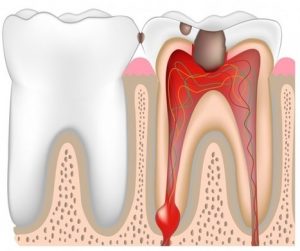

เนื่องจากการปล่อยให้ฟันผุเป็นเวลานานและไม่ได้รับการรักษา จนอักเสบลึกเข้าไปใกล้โพรงประสาทฟัน, ฟันแตก ฟันหัก หรือฟันมีรอยร้าว จากการบดเคี้ยวอาหาร หรือจากอุบัติเหตุ ทำให้เชื้อแบคทีเรียในน้ำลายเข้าไปในโพรงประสาทฟันและทำอันตรายต่อประสาทฟัน รวมทั้งโรคเหงือกอักเสบเรื้อรัง และการที่ฟันถูกกระแทกแรงๆ ก็ทำให้ส่วนปลายประสาทฟันตายได้ ทำให้เกิดการอักเสบเป็นหนองที่รากฟันตามมา และเริ่มมีอาการปวดฟัน โดยอาจจะปวดแบบเป็นๆ หายๆ , ปวดเป็นระยะ หรือปวดอย่างรุนแรง ร่วมกับมีอาการเหงือกบวม